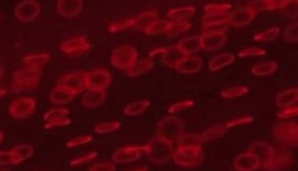

Chimiştii din România au creat, în premieră mondială, sânge artificial şi sânge incolor (VIDEO)